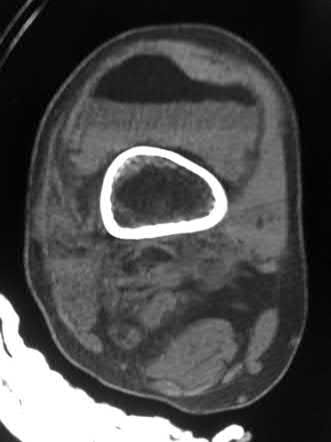

A 33-year-old secretary presents three months after a motor vehicle collision with a mild asymmetry to her sternal area and difficulty swallowing. She denies any complaints of respiratory distress or upper extremity paresthesias. Her upper extremity neurovascular exam shows no deficits. A 3-D computed tomography image is shown in Figure A. What is the most appropriate treatment for this patient?

The clinical presentation is consistent with a chronic sternoclavicular dislocation, which is defined as being greater than 3 weeks old. The 3D CT image shows posterior displacement of the medial clavicle relative to the sternum. Chronic anterior dislocations are recommended to be treated conservatively, especially if not symptomatic, but as this is a posterior dislocations, current recommendations are to treat them with reduction in order to avoid delayed issues with the medial clavicle interacting with the mediastinal structures.

The review article by Wirth and Rockwood notes the following complications with posterior dislocation: respiratory distress, venous congestion or arterial insufficiency, brachial plexus compression, and myocardial conduction abnormalities. They recommend reconstruction of the costoclavicular ligaments with resection of the medial claviclar head as needed for unstable or symptomatic injuries.